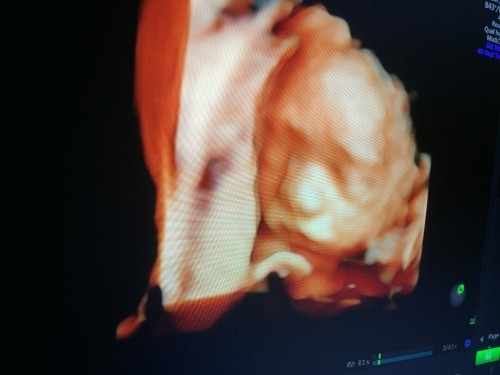

ซาวน์4มิติ 26W ทีมสิงหาคม64

ซาวน์4มิติ 26W ทีมสิงหาคม64 น้องหลบเก่ง แม่ๆท่านไหน เห็นชัดกว่านี้ไหม มาแชร์กันค่ะ